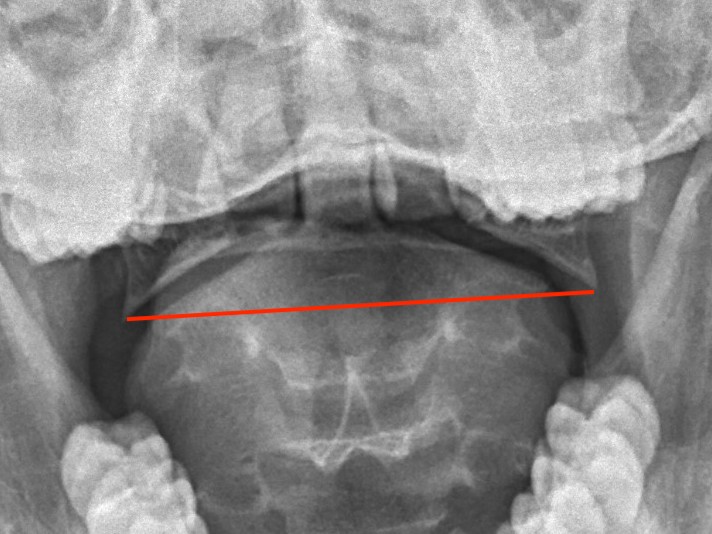

LMD

Lateral mass displacement

LMD 1LMD 2

Increased lateral mass displacement of 8 mm